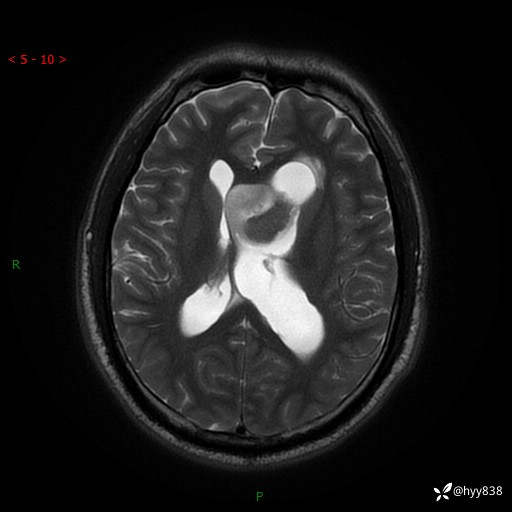

颅脑MRI平扫+增强